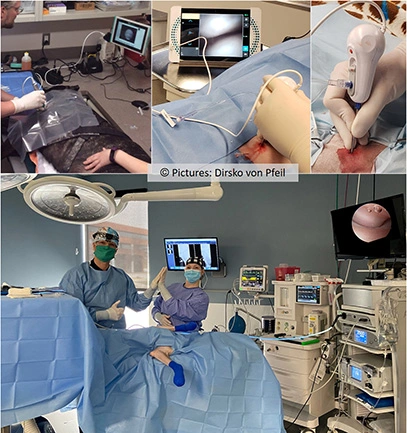

Gelenksspiegelungen, Arthroskopie

Gelenksspiegelungen, Arthroskopie (Klassische Arthroskopie und Nano- oder Nadelarthroskopie)

Schulter, Ellenbogen, Karpalgelenk, Hüfte, Knie, Sprunggelenk

Die klassische Arthroskopie erlaubt Gelenkinspektion und gleichzeitige Behandlung von Gelenkskrankheiten mittels einer hochauflösenden Kamera.

Bei der Nano- oder Nadelarthroskopie wird mittels einer Kamera, die kleiner ist als ein Bleistift, das Gelenk untersucht.

Nano- oder Nadelarthroskopie (oben) und klassische Arthroskopie (unten) erlauben Diagnose und oft auch Behandlung via minimal invasivem Eingriff.